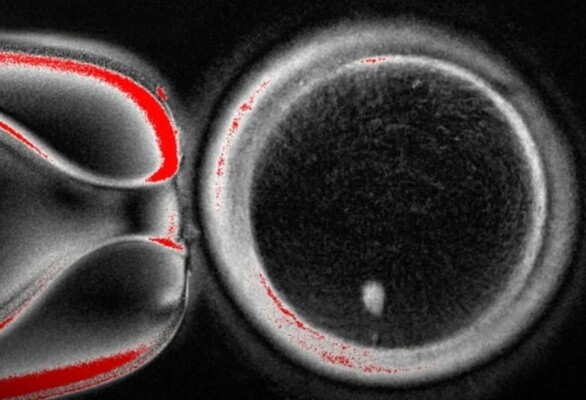

أُجريت هذه الدراسة في Oregon Health & Science University، حيث تمكن العلماء من تحقيق إنجاز مهم في مجال علوم التكاثر، وتعتمد التقنية على استبدال نواة بويضة متبرَّع بها بنواة مأخوذة من خلية جلد بشرية، ما يسمح لسيتوبلازم البويضة بإعادة برمجة المادة الوراثية الموجودة داخلها، وخلال هذه العملية، أُجبر الحمض النووي القادم من خلايا الجلد على التخلص من نصف كروموسوماته، في خطوة تحاكي العملية البيولوجية الطبيعية التي تحدث أثناء تكوين الخلايا التناسلية لدى البشر.

وبعد تكوين هذه الخلايا الشبيهة بالبويضات داخل المختبر، قام الباحثون بتخصيبها باستخدام تقنيات الإخصاب المخبري المعروفة، وتمكّن بعض هذه الأجنة الناتجة من الاستمرار في النمو لمدة تصل إلى ستة أيام، وهي المرحلة التي يُجرى عندها عادة نقل الأجنة في عمليات أطفال الأنابيب.